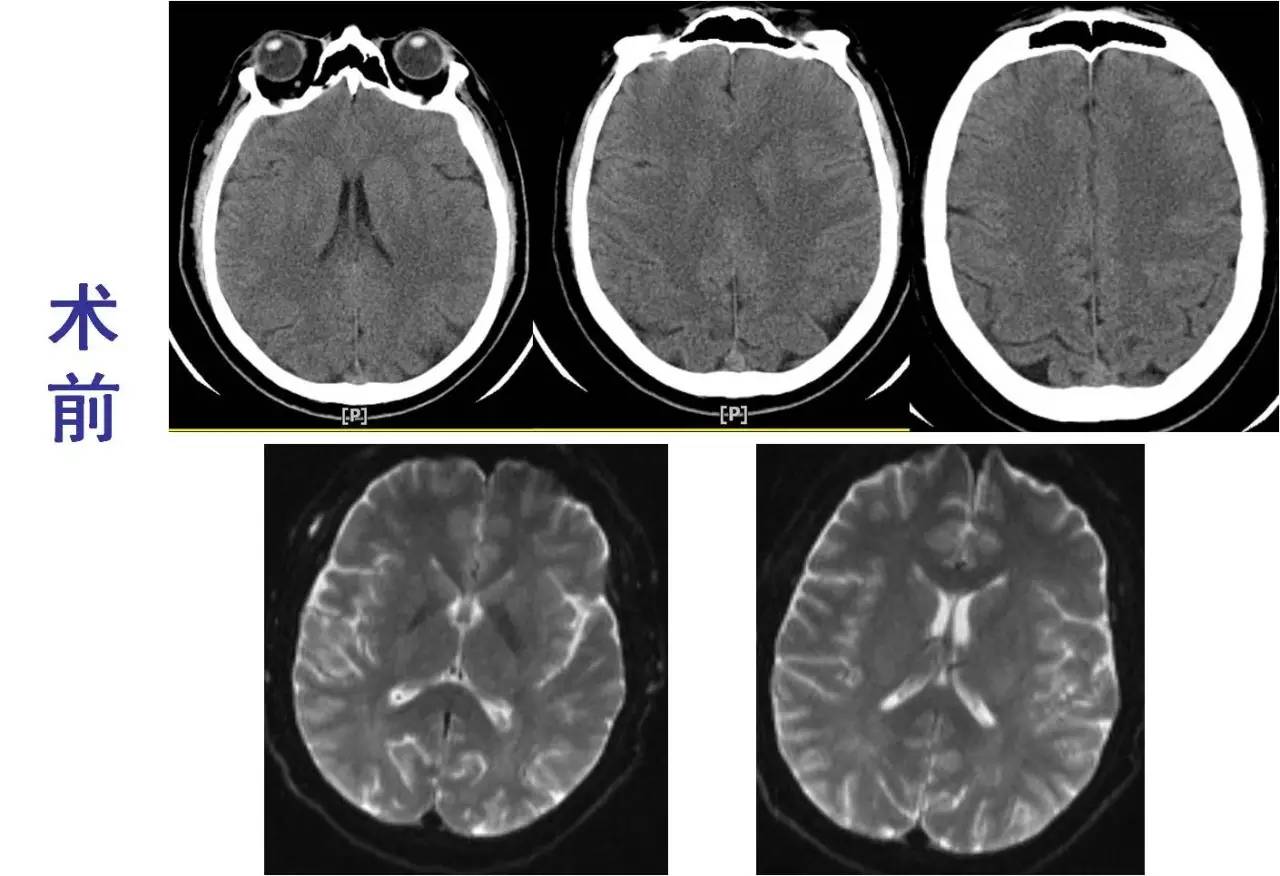

》CT:颅内未见出血;

》DSA:左侧大脑中动脉闭塞。

术前

3